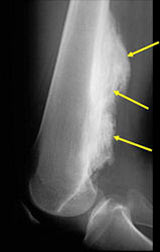

Radiographic imaging is used to help form a diagnosis. These include X-Ray, MRI, CT.

An example of an MRI is shown.